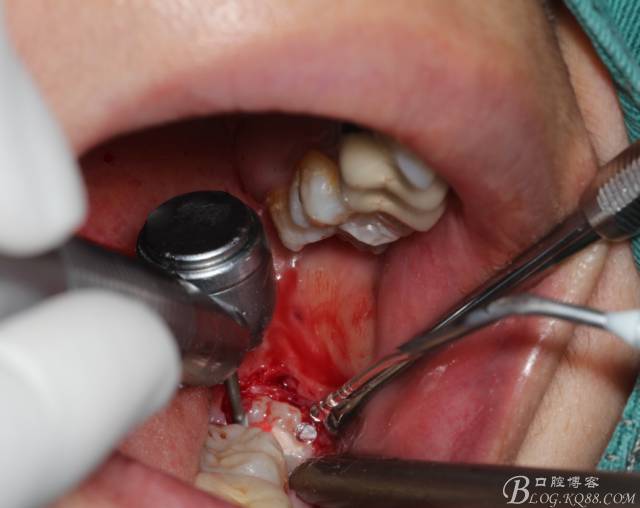

補(bǔ)完牙后,準(zhǔn)備撥除阻生智齒了。

先分析智齒的情況,口內(nèi)直觀是半個(gè)牙尖都沒露出來,差一點(diǎn)就完全埋伏了。磨牙后墊的可操作面積中規(guī)中紀(jì),X全景片示三類阻生,根冠比例是1:1,非融合根,近中根壓下頜管。

切開:角形切口,這個(gè)位置切開我喜歡更易操作12#刀。